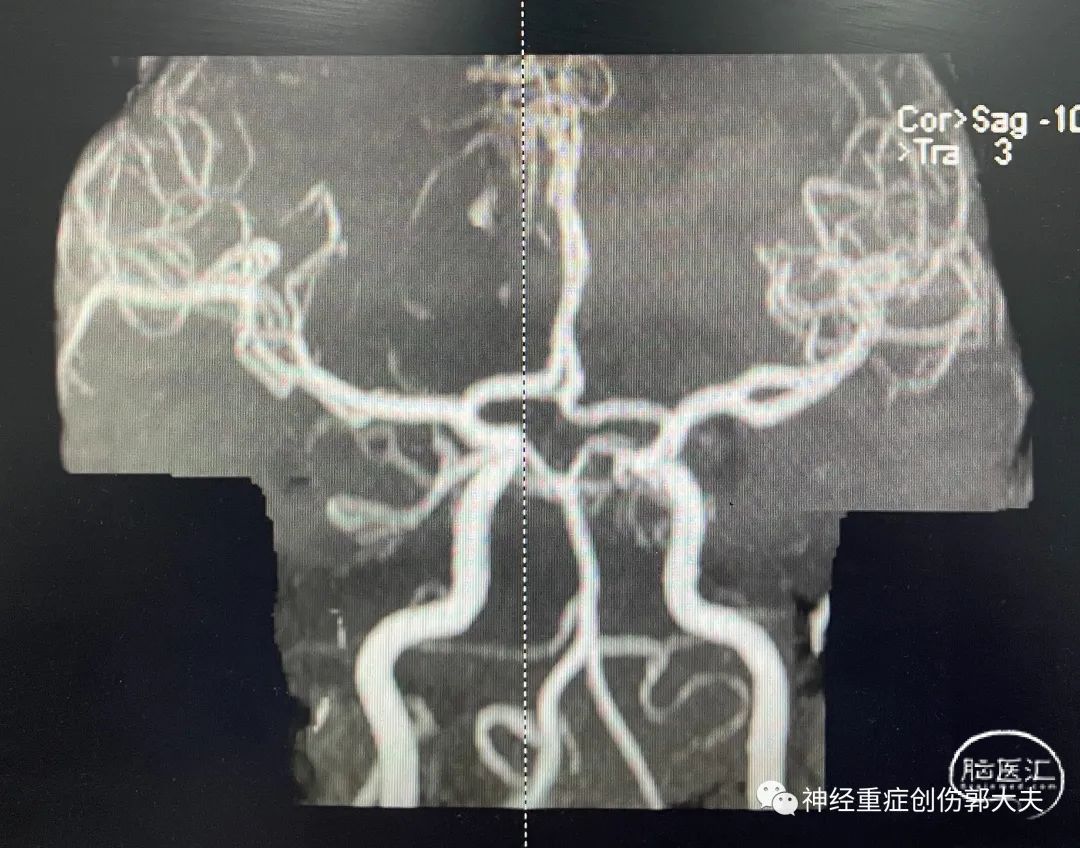

患者女性,70岁,主因“意识障碍10小时”入院。神志昏睡,GCS10分。头颅CT显示右侧额顶叶脑出血破入脑室,蛛网膜下腔出血。

完善全脑血管造影后未见明显颅内动脉瘤及血管畸形,急诊行右额颞开颅血肿清除+去骨瓣减压术。